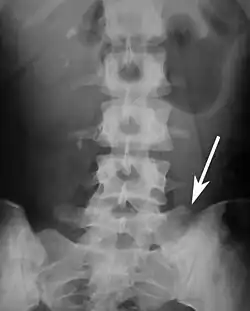

Lumbarization and sacralization

Lumbarization is an anomaly in the spine. It is defined by the nonfusion of the first and second segments of the sacrum. The lumbar spine subsequently appears to have six vertebrae or segments, not five. This sixth lumbar vertebra is known as a transitional vertebra. Conversely the sacrum appears to have only four segments instead of its designated five segments. Lumbosacral transitional vertebrae consist of the process of the last lumbar vertebra fusing with the first sacral segment. [1] While only around 10 percent of adults have a spinal abnormality due to genetics, a sixth lumbar vertebra is one of the more common abnormalities. [2]

Sacralization of the fifth lumbar vertebra (or sacralization) is a congenital anomaly, in which the transverse process of the last lumbar vertebra (L5) fuses to the sacrum on one side or both, or to ilium, or both. These anomalies are observed in about 3.5 percent of people, and it is usually bilateral but can be unilateral or incomplete (ipsilateral or contralateral rudimentary facets) as well. Although sacralization may be a cause of low back pain, it is asymptomatic in many cases (especially bilateral type). Low back pain in these cases most likely occurs due to biomechanics. In sacralization, the L5-S1 intervertebral disc may be thin and narrow. This abnormality is found by X-ray.

Sacralization of L6 means L6 attaches to S1 via a rudimentary joint. This L6-S1 joint creates additional motion, increasing the potential for motion-related stress and lower back pain/conditions. This condition can usually be treated without surgery, injecting steroid medication at the pseudoarticulation instead. Additionally, if L6 fuses to another vertebra this is increasingly likely to cause lower back pain.[3] The presence of a sixth vertebra in the space where five vertebrae normally reside also decreases the flexibility of the spine and increases the likelihood of injury.[4]